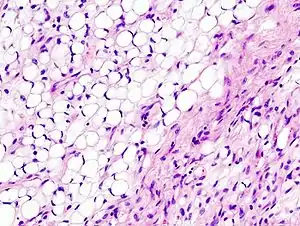

The diagnosis is established by histologic examination of the tissue, i.e., biopsy or excision. Lipoblasts are often present; these are cells with an abundant clear multivacuolated cytoplasm and an eccentric darkly staining nucleus that is indented by the vacuoles.

Micrograph of a myxoid liposarcoma, H&E stain

| Micrograph of myxoid liposarcoma, H&E stain | |